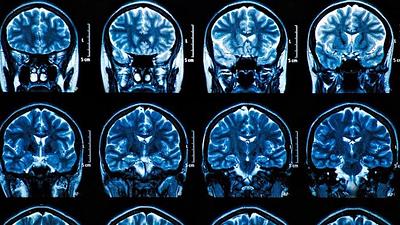

Estudo sugere relação entre bactéria da gengiva e Alzheimer

Cientistas acreditam ter descoberto possível causa da doença neurodegenerativa que é um dos maiores mistérios da medicina. Primeiros testes mostram resultados positivos, inclusive de reparação de neurônios danificados.